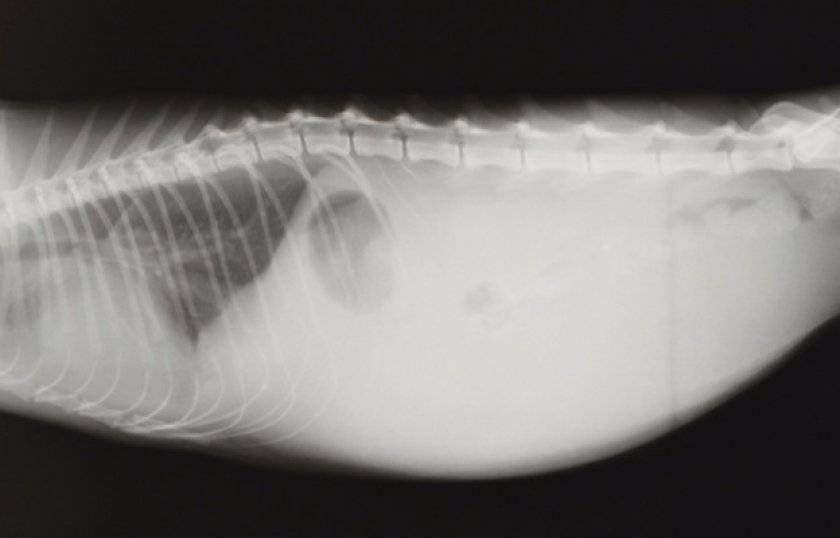

Экссудативный («мокрый») сценарий связан с выработкой и выходом значительного объема жидкости, поступающей в брюшную или грудную полость. Заметить этот процесс просто:

- начинается одышка (если вещество попало в грудную полость, дав тем самым начало плевриту);

- также может увеличиться живот; в тяжелых случаях туда может попасть до 1 литра экссудата;

- ультразвуковое и рентгенологическое обследование области живота. При помощи данных методов диагностирования можно с максимальной точностью обнаружить наличие воспалительных процессов, а также поражений с гранулематозным характером во внутренних органах;